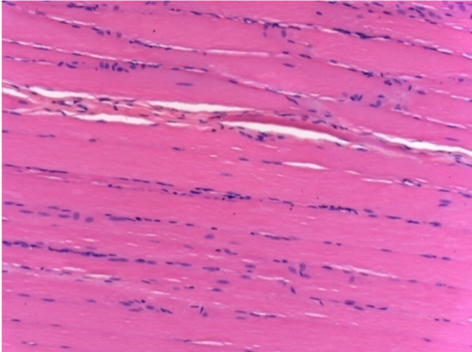

L: Pretibial-Sin tratamiento

R: Pretibial-Después de 0,1 ml de NaCl 0,9% IM

10 días después de la inyección de Endopeel 0,1 ml en el músculo pretibial derecho.

Aquí puede ver la formación de las vacuolas que están rodeadas de linfocitos. Las vacuolas son diferentes a la necrosis tisular. La presencia de linfocitos está relacionada con la permeabilidad de las membranas celulares.